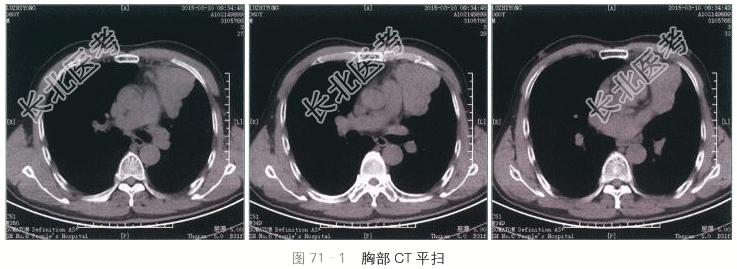

- [材料题] 患者,男性,60岁,胸前区隐痛不适半年。体格检查:呼吸音清,胸前区无明显扣痛。实验室检查:血常规、肝肾功能及肿瘤标志物均正常。胸部CT扫描(见图71-1~图71-3):提示左前纵隔软组织密度肿块,形态不规则,边缘可见分叶和波浪样改变,密度较均匀,CT值约45Hu,增强后动脉早期轻度强化,CT值约54Hu,延迟期可见显著持续渐进性强化,CT值约82Hu。肿块局部层面与肺动脉及左心耳分界不清,脂肪间隙消失。

读片分析:本例患者的病灶定位于前纵隔,前纵隔好发的肿瘤及肿瘤样病变包括胸骨后甲状腺肿、胸腺囊肿、胸腺瘤、胸腺癌、淋巴瘤、生殖细胞肿瘤及心包囊肿。诊断的关键在于观察病灶和周围结构的分界和关系,肿块成分和强化程度,以及患者的年龄。本例患者的病灶上缘与甲状腺无直接联系,可除外甲状腺来源病变。病灶在CT扫描表现为实质性肿块,可除外囊肿性病变。增强后表现为不均匀的渐进性强化,未看见脂肪或钙化成分,而且患者年龄较大,因此典型的畸胎瘤或精原细胞瘤的可能性相对较小。增强后肿块局部可见与周围大血管的边界不清,脂肪间隙消失,提示病变具有一定的侵袭性,可符合侵袭性胸腺瘤或淋巴瘤表现。但患者中纵隔及肺门未见明显肿大淋巴结。因此最终诊断将侵袭性胸腺瘤放在首位。手术病理证实该例患者为侵袭性胸腺瘤。